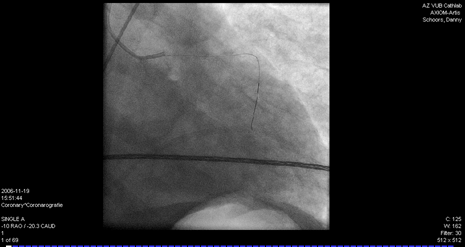

3. L’appareil à rayons X fait des clichés des coronaires selon différents angles et les images s’affichent sur les moniteurs. Le cathéter guide et le fil guide sont tous deux bien visibles sur le moniteur.

Avant (figure 1) et après (figure 2) la dilatation